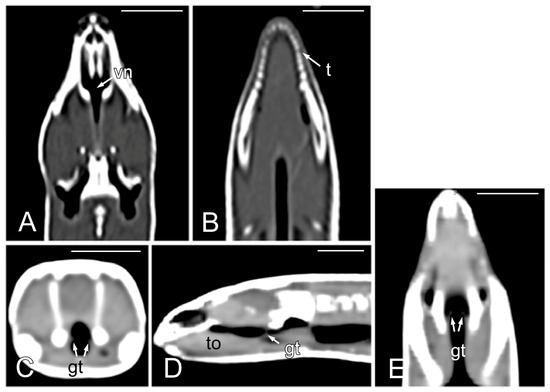

In the oral cavity, a wide overture that coincides with the vomeronasal organ and the choanae opening stands out (Figure 3A,B). The presence of the glottis, quite cranial in the oral cavity, and visible when the mouth is opened (Figure 3C), is noteworthy. The upper airways also include a larynx and pharynx that do not show special details. To complete the macroscopic description of the oral cavity, the cone-shaped, slightly asymmetrical teeth and the forked tongue should also be highlighted (Figure 3C).

Figure 3.

The images of the oral cavity of Pseudopus apodus showing the opening of the vomeronasal organ and the choanae (A,B), the tongue (C), and the glottis (C). See the list for abbreviations. Bar = 1 mm.

The opening of the vomeronasal organ together with the choanae was identified in the dorsal plane as a V-shaped structure delimited by thin hyperattenuating margins (Figure 4A). The teeth were more distinctly evaluated in the dorsal plane (Figure 4B). The tongue appeared as a hypoattenuating structure located in the ventral part of oral cavity and was more clearly visible in the sagittal plane (Figure 4D). The glottis (Figure 4C–E) was identified as a thin, soft tissue structure with a central opening between the oral and pharyngeal cavities. Although it was visible in the transverse, sagittal, and dorsal planes, it was easier to identify in the latter two.

Figure 4.

The CT images of Pseudopus apodus in the dorsal (A,B,E), transverse (C) and sagittal (D) planes showing the opening of the vomeronasal organ and the choanae (A), teeth (B), tongue (D) and glottis (C–E). See the list for abbreviations. Bar = 10 mm.